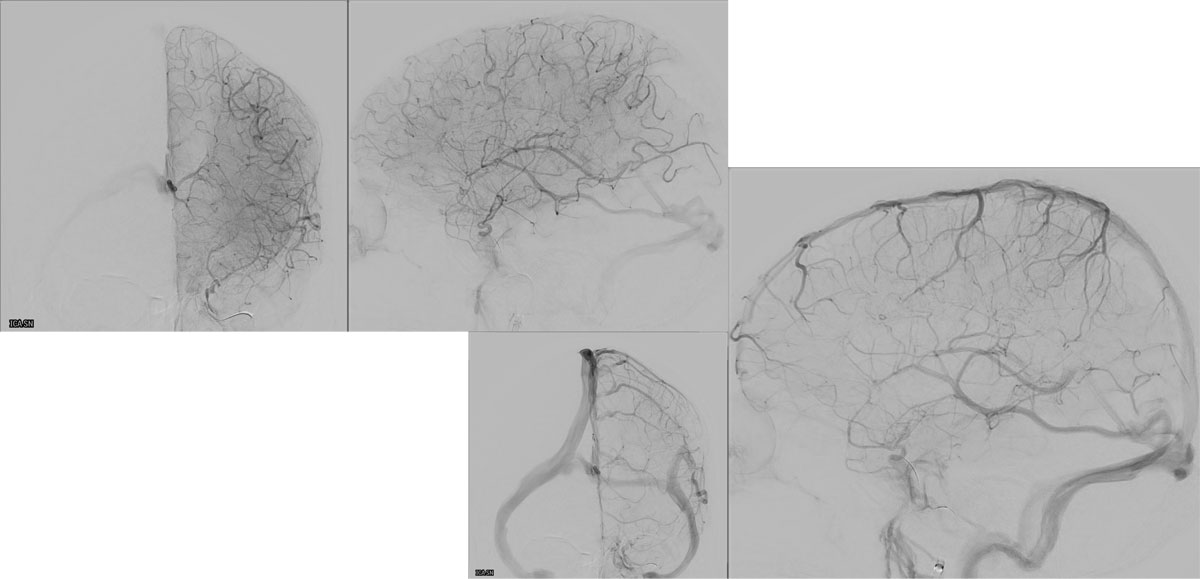

DSA

L - VERT

L - ICA